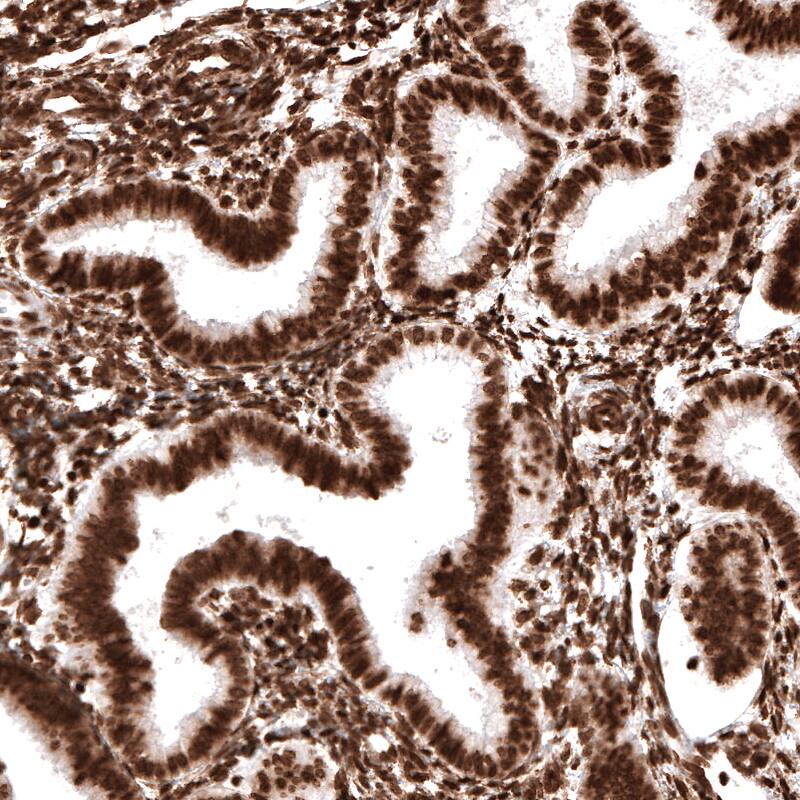

Staining of human endometrium shows strong nuclear immunoreactivity in glandular and stromal cells.